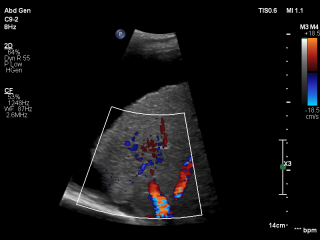

Die Ultraschalldiagnostik ist in allen Bereichen der Medizin eine der wesentlichen Säulen der bildgebenden Diagnostik und ist ein essentieller Bestandteil der täglichen Routine. Diese bildgebende Technik gehört zu der am schnellsten wachsenden Verfahren in der Medizin. Der medizinische Ultraschall, liefert in vielen Bereichen beeindruckende Fortschritte und führt zu einer Steigerung des aktuellen Wissens über moderne Diagnose- und Interventionstechniken. Für eine optimale Vorbereitung auf diesen Entwicklungstrends, Bedarfs es einer kontinuierlichen Aus- und Weiterbildung.